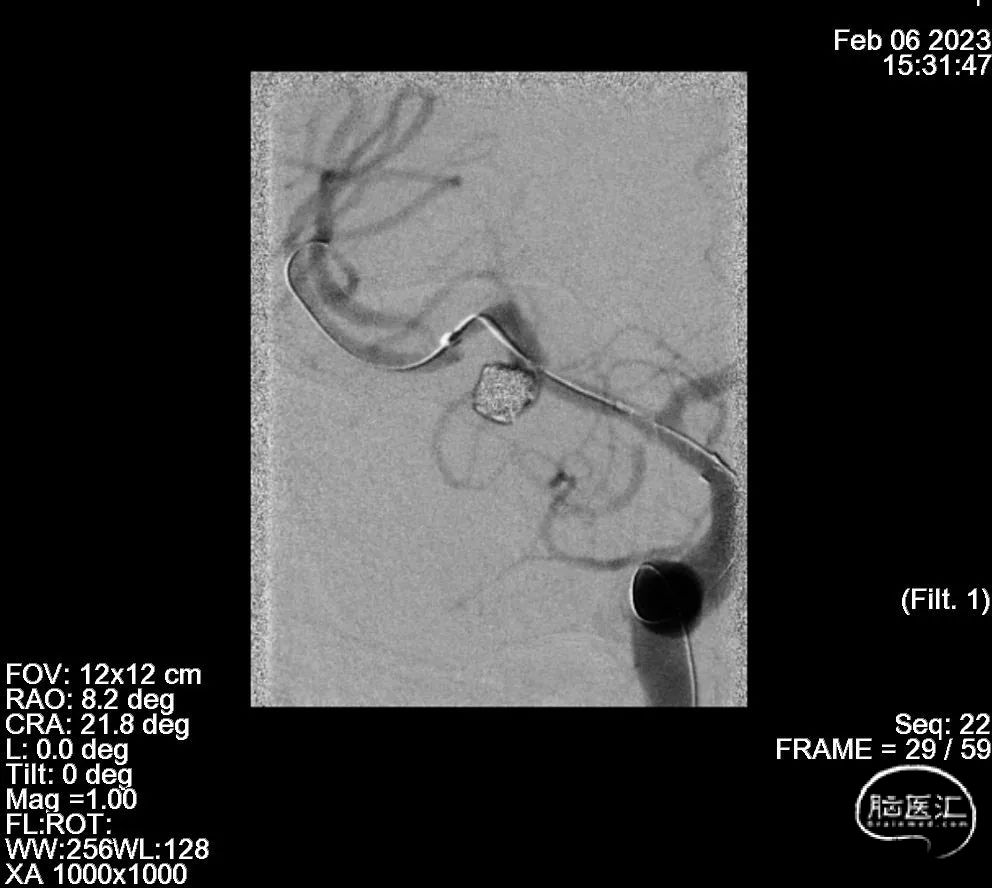

支架辅助动脉瘤栓塞

2、支架辅助动脉瘤栓塞术

4、ENTERPRISE2 4.0mm*30mm

6、Axium Prime 3mm*8cm、2mm*6cm

7、通桥4mm*8cm、2.5mm*4cm、1mm*4cm、1mm*4cm

治疗过程

血管成形

治疗结果

术后3月DSA

1.特色:优先扩张狭窄血管,为微导管进入瘤腔提供条件;处理完动脉瘤后再次使用较大球囊扩张狭窄血管预防再狭窄;